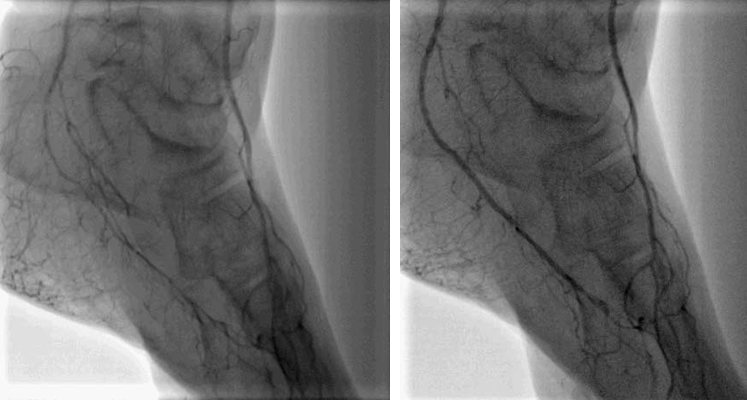

血管内手術

- 大動脈狭窄 【写真】

- 高位大動脈閉塞(Leriche synd) 【写真】

- 腸骨動脈完全閉塞(右) 【写真】

- 腸骨動脈狭窄 【写真】

- 浅大腿動脈狭窄 【写真】

- 浅大腿動脈閉塞 【写真】

- 3枝閉塞 【写真】

- 脛骨腓骨動脈幹(peroneal trunk) 【写真】

- 後脛骨動脈(posterior tibial artery) 【写真】